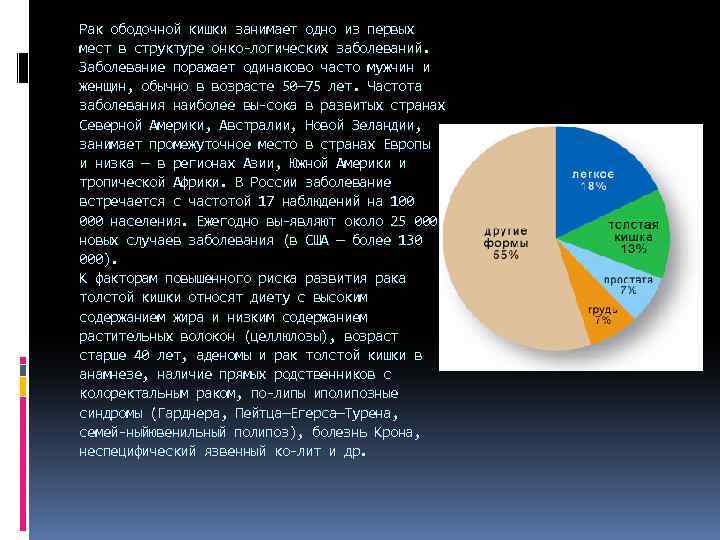

Рак ободочной кишки занимает одно из первых мест в структуре онко логических заболеваний. Заболевание поражает одинаково часто мужчин и женщин, обычно в возрасте 50— 75 лет. Частота заболевания наиболее вы сока в развитых странах Северной Америки, Австралии, Новой Зеландии, занимает промежуточное место в странах Европы и низка — в регионах Азии, Южной Америки и тропической Африки. В России заболевание встречается с частотой 17 наблюдений на 100 000 населения. Ежегодно вы являют около 25 000 новых случаев заболевания (в США — более 130 000). К факторам повышенного риска развития рака толстой кишки относят диету с высоким содержанием жира и низким содержанием растительных волокон (целлюлозы), возраст старше 40 лет, аденомы и рак толстой кишки в анамнезе, наличие прямых родственников с колоректальным раком, по липы иполипозные синдромы (Гарднера, Пейтца—Егерса—Турена, семей ныйювенильный полипоз), болезнь Крона, неспецифический язвенный ко лит и др.